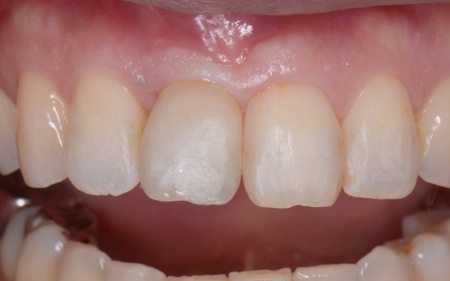

50代女性 インプラント・矯正・被せ物治療で見た目と噛み合わせを改善した症例

④矯正終了後に右上下奥歯の合わなくなった被せ物を除去し、自然な白さで強度もあるジルコニアセラミッククラウンを装着する。

最後に装着したジルコニアセラミッククラウンが歯に合っているか、噛み合わせに問題がないかを確認し、治療を終了しました。